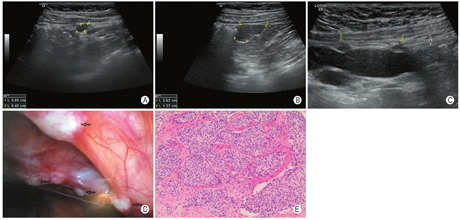

病例1,男,8岁5个月,因间歇性腹部钝痛2个月余来院就诊,超声检查发现腹腔及盆腔数处不规则低回声包块,最大者位于盆腔,长径4.8 cm;包块形态不规则,内部可见钙化斑,较大包块中央有少量液化,包块可见较丰富血流信号;肠间隙有少量清亮游离积液。对肿块进行手术切除,术后病理显示肿瘤细胞呈小圆形、巢状分布,核分裂象多见,周围见丰富纤维间隔(图1)。免疫组化:D99+、Desmin+、CK+、EMA+、WT1散在+、SYN-、MyoD1-、Desmin+、Ki-67约50%。基因检测显示EWSR1(22q12)基因断裂。病理诊断为促结缔组织增生性小圆细胞肿瘤。术后规律化疗,每隔1个月左右超声定期随访。4个月后超声检查发现腹膜复发灶,随访中逐渐增大(图1A,B)、增多,累及多个组织器官。行第二次手术,术中可见肿瘤弥漫种植于腹腔及盆腔的腹膜、网膜、肠系膜表面(图1D)及肠壁,膀胱壁浆膜侧,并在肝脏、脾脏等脏器内发现多发病灶,切除所有肉眼可见病灶,继续化疗。术后8个月超声检查再次发现复发病灶,随访中逐渐进展,间隔11个月后再次手术,切除肉眼可见病灶,术后5个月后多组织脏器再次出现多发复发病灶,并迅速增大,部分病灶逐渐包绕肠管、侵犯输尿管(图1C)。发病2年4个月后患儿死亡。